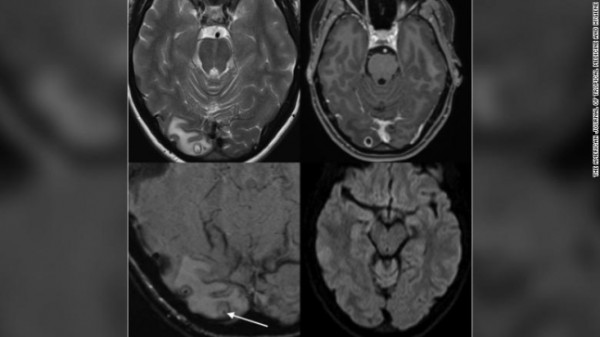

뇌 자기공명영상(MRI)을 찍어본 연구진은 A씨의 뇌에서 종양이 아닌 물혹을 발견했다. 인간의 세포 조직으로 형성된 물혹이 아니라는 판단을 내린 연구진이 정밀 검사를 시행한 결과, 기생충들이 그 안에서 자라고 있었다는 사실을 확인했다.